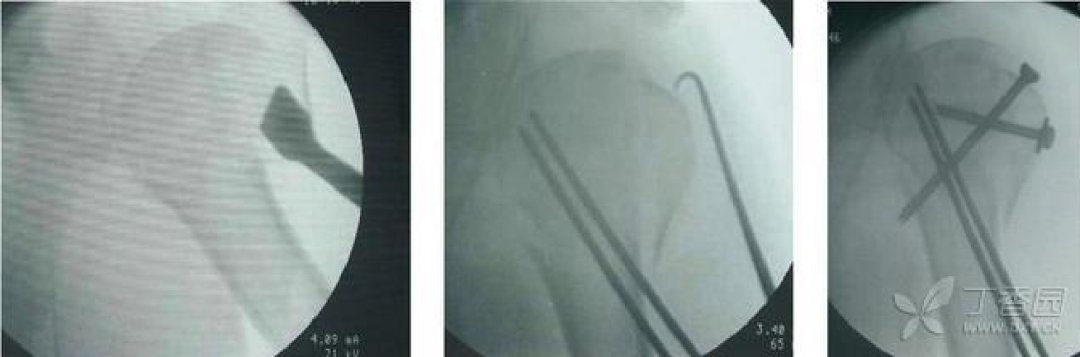

1、经皮穿针内固定适应证:此技术相对微创,发生骨坏死的机率相对较小,但稳定性不足,技术要求高。可用于不稳定的两部分外科颈骨折,也可用于更为复杂的三部分骨折或外展崁插的四部分骨折

一例外展崁插四部分骨折的前后位片:

器械辅助下复位骨折,经皮穿针内固定术的最终效果

该技术一般需要患者具有较好的骨密度,粉碎程度轻,结节完整,内侧壁支撑好,更为关键的是患者应具有较好的依从性。

预后:此技术一般可获得良好的愈合和功能恢复,如果术中无法获得良好的复位,应进行切开复位。